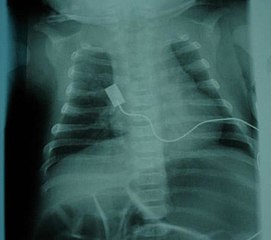

| 제1형 | 베르드니히-호프만병 (Werdnig-Hoffmann disease) | 출생 후 6개월 미만 | 가장 흔하고 심각한 유형 (약 50%). 전신적인 심한 근력 저하 및 근육긴장저하(플로피 인펀트). 임신 중 태동 약화 가능성. 도움 없이 앉기 불가능, 머리 가누기 불가능. 안면근 약화, 빨기/삼키기 어려움, 흡인, 호흡 부전 동반. 늑간근 약화로 인한 기이 호흡(흡기 시 흉부 함몰). 혀의 섬유속성 연축, 심부건 반사 소실. 인공 호흡기 없이는 평균 6~9개월 생존, 대부분 2년 이내 사망. |

| SMA 1 (영아형) | 베르드니히-호프만병 | 0~6개월 | 가장 흔한 형태로 환자의 약 50%를 차지한다. 생후 몇 주 또는 몇 달 내에 질병이 나타나며, 빠르게 진행되어 다양한 근육 그룹의 기능 장애를 일으킨다. 영아는 도움 없이 앉는 법을 배우지 못하고 점진적으로 근육 기능을 상실한다. 주요 사망 원인은 호흡 근육 기능 부전으로 인한 폐렴(특히 흡인성 폐렴)이다. 조기 호흡 지원 및 약물 치료 없이는 대부분 생후 2년을 넘기지 못한다. 그러나 적절한 호흡 지원을 받으면 증상이 덜 심한 일부 환자(SMA 1형의 약 10%)는 약물 치료 없이도 청소년기 및 성인기까지 생존하는 경우가 있으며, 이 경우 지속적인 간호가 필요하다. 특징적인 증상으로는 심한 전신 근긴장저하 (플로피 인펀트), 머리 제어 불가능, 안면근육 약화, 수유 및 연하 곤란, 혀 근육의 떨림(섬유 다발 연축), 기이 호흡 등이 있다. 심부건 반사는 소실된다. | 253300 |

호흡계는 척수성 근위축증(SMA)에서 가장 흔하게 영향을 받는 계통이며, 특히 SMA 0/1형 및 2형에서 호흡기 합병증은 주요 사망 원인이다. SMA 3형도 드물지만 유사한 호흡기 문제를 겪을 수 있다.[58] 이러한 합병증은 신경 자극 부족으로 인해 늑간근이 약해져서 발생하며, 횡격막은 상대적으로 덜 영향을 받는다.[58] 약해진 근육은 호흡과 기침 능력을 완전히 회복하기 어렵다. 이로 인해 호흡이 힘들어지고, 충분한 산소를 얻지 못하거나 얕은 호흡을 하게 되며, 기도 분비물을 효과적으로 제거하지 못할 위험이 있다. 이러한 문제는 근육이 더 이완되는 수면 중에 더 흔하게 나타난다. 또한, 인두의 삼킴 근육(연하 근육)이 약해지면 음식물이나 분비물이 기도로 넘어가는 흡인이 발생할 수 있으며, 약한 기침 능력과 결합되어 폐렴과 같은 감염 위험을 높인다.[59]호흡 관리를 위해서는 다음과 같은 방법들이 사용된다.